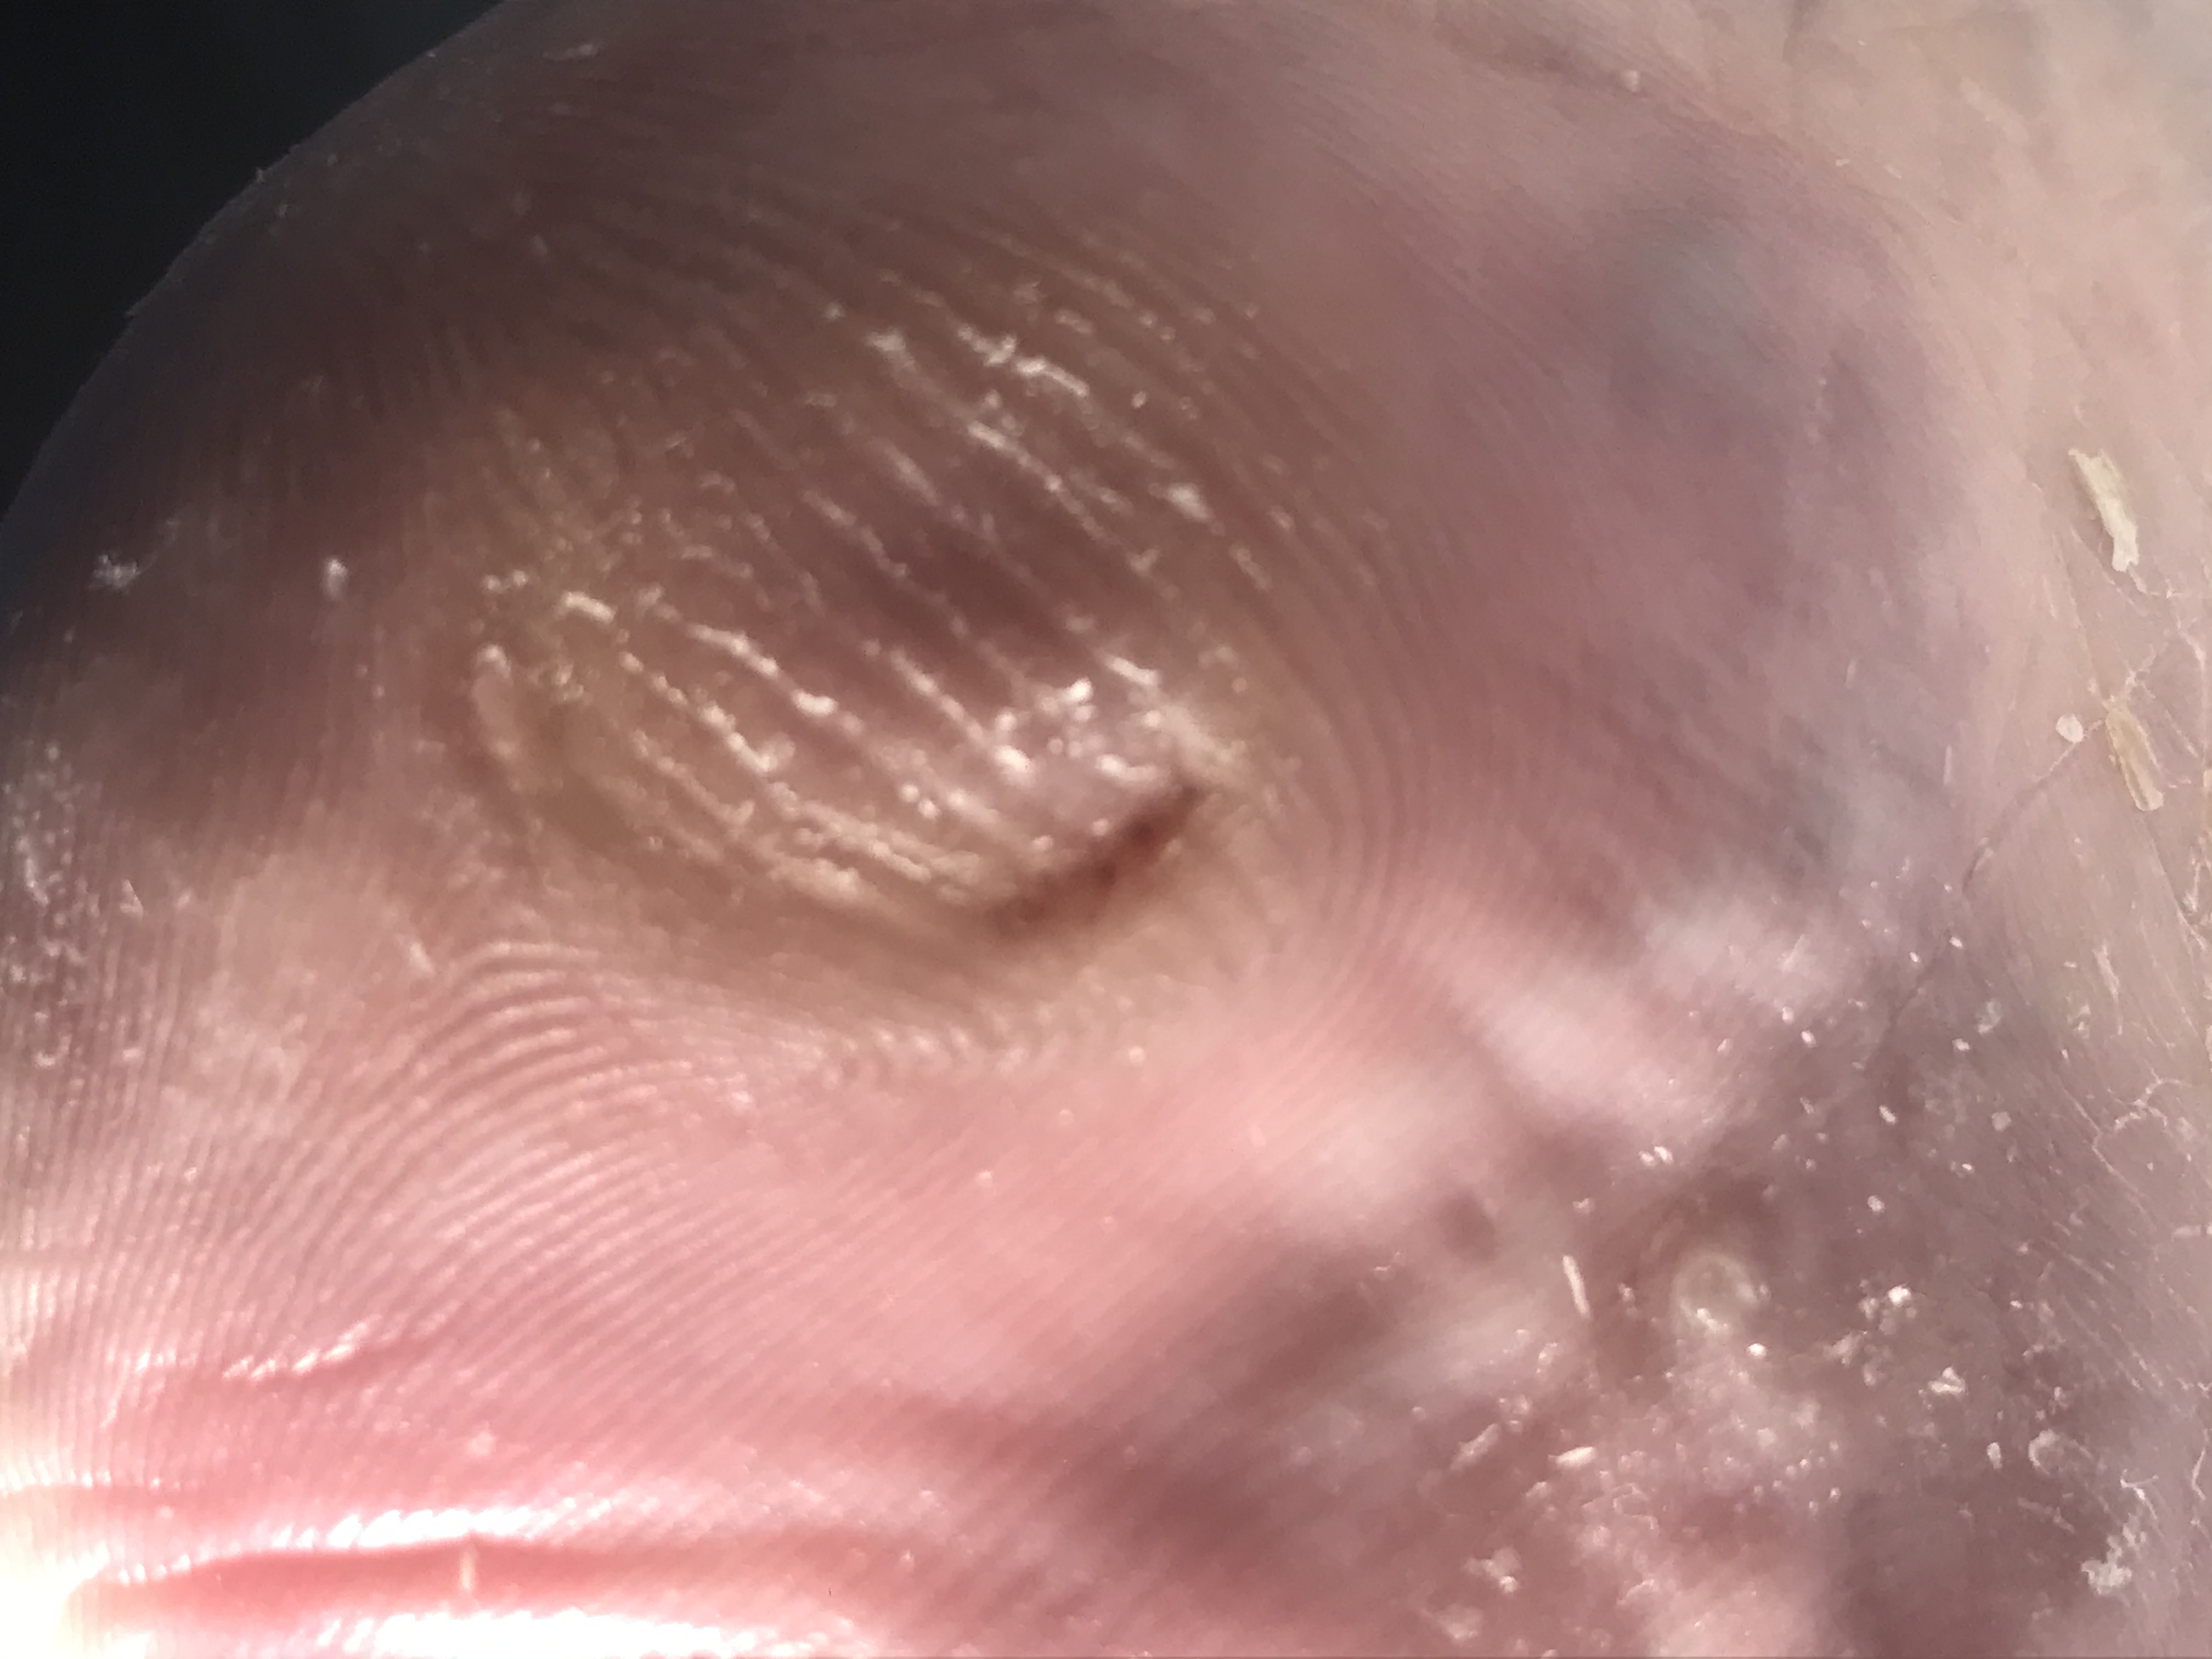

Cor

Verrue